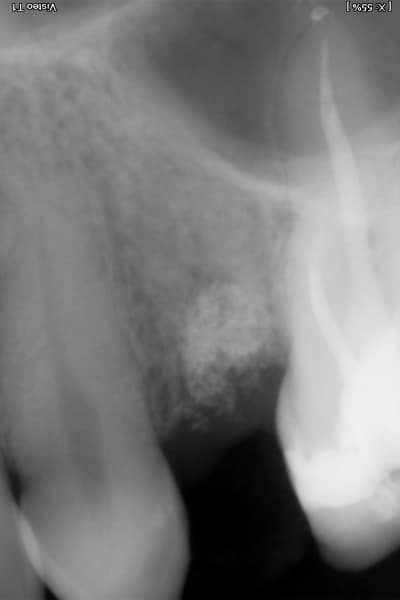

Zubní implantát je alternativním protetickým řešením, neboť chybějící zuby lze kromě klasického můstku klinicky vhodněji nahradit zubním implantátem, který splňuje všechny funkce původního zubu a navíc je jeho přirozenou a věrnou kopií, bez nutnosti zbrousit (degradovat) jiné okolní zuby (jako v případě můstku).